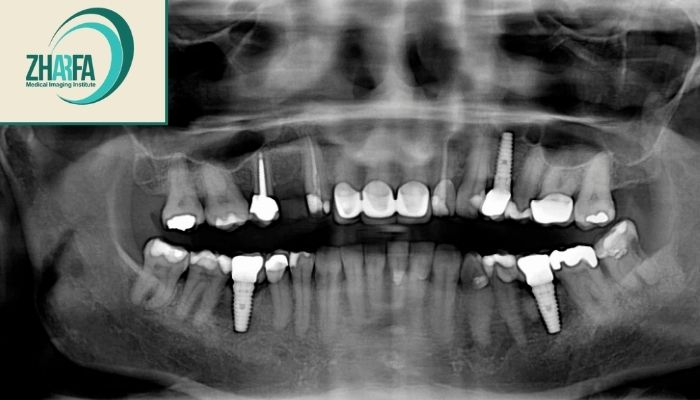

عکس OPG: برای نمایش وضعیت کلی فک و دندانها در یک تصویر.

ارزیابی قبل از درمانهای پروتزی: بررسی وضعیت فک و دندانها قبل از ایمپلنت یا پروتز.

نحوه انجام رادیوگرافی پانورامیک دندانها